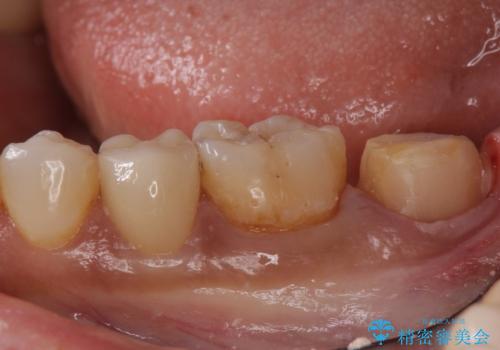

- 左下7 仮歯+e-maxクラウン:11,000円+77,000円費用は治療当時の料金となります

今回の場合、虫歯の大きさが大きく本来であれば歯茎に対しても治療をすることが検討されケースですが、ご希望されなかったため被せ物のみでの治療となりました。